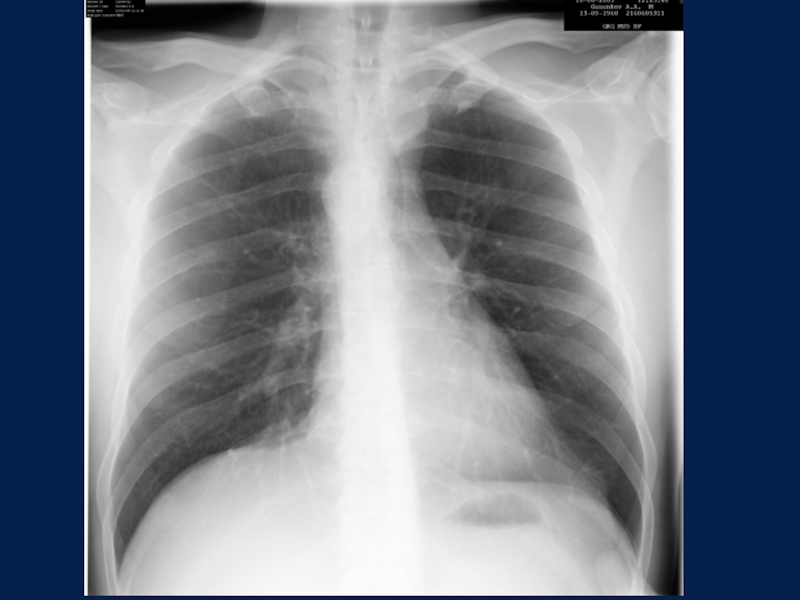

Слайд 5Цель исследования:

изучение состояния легких при подозрении на любое их

заболевание или повреждение

Укладка для выполнения снимка:

снимок выполняют в положении больного

стоя (или сидя, в зависимости от состояния) у специальной вертикальной стойки;

больной плотно прижимается грудью к кассете, слегка согнувшись вперед.

Рентгенография ОГК

Снимок легких в прямой передней проекции

Цель исследования: изучение состояния легких при подозрении на любое их заболевание или повреждениеУкладка для выполнения снимка:снимок выполняют

Слайд 32ОБЗОРНАЯ РЕНТГЕНОГРАФИЯ ОРГАНОВ ГРУДНОЙ ПОЛОСТИ

Н О Р М

ОБЗОРНАЯ РЕНТГЕНОГРАФИЯ ОРГАНОВ ГРУДНОЙ ПОЛОСТИ  Н О Р М А